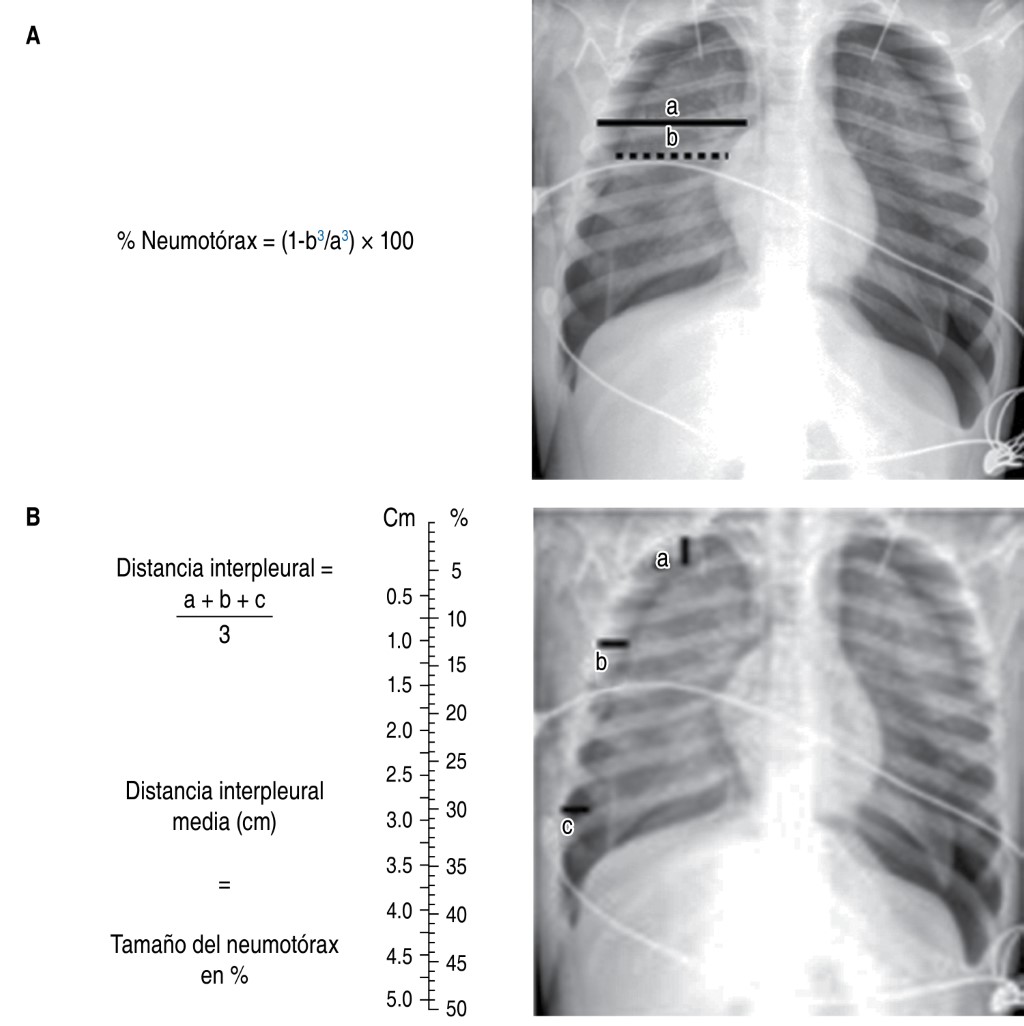

Existen otras proyecciones radiológicas como son: la radiografía en espiración, la cual detecta pequeños neumotórax y atrapamiento aéreo localizado asociado a cuerpos extraños; la proyección en decúbito lateral con rayo horizontal que evalúa líquido libre en la cavidad pleural, entre otras.